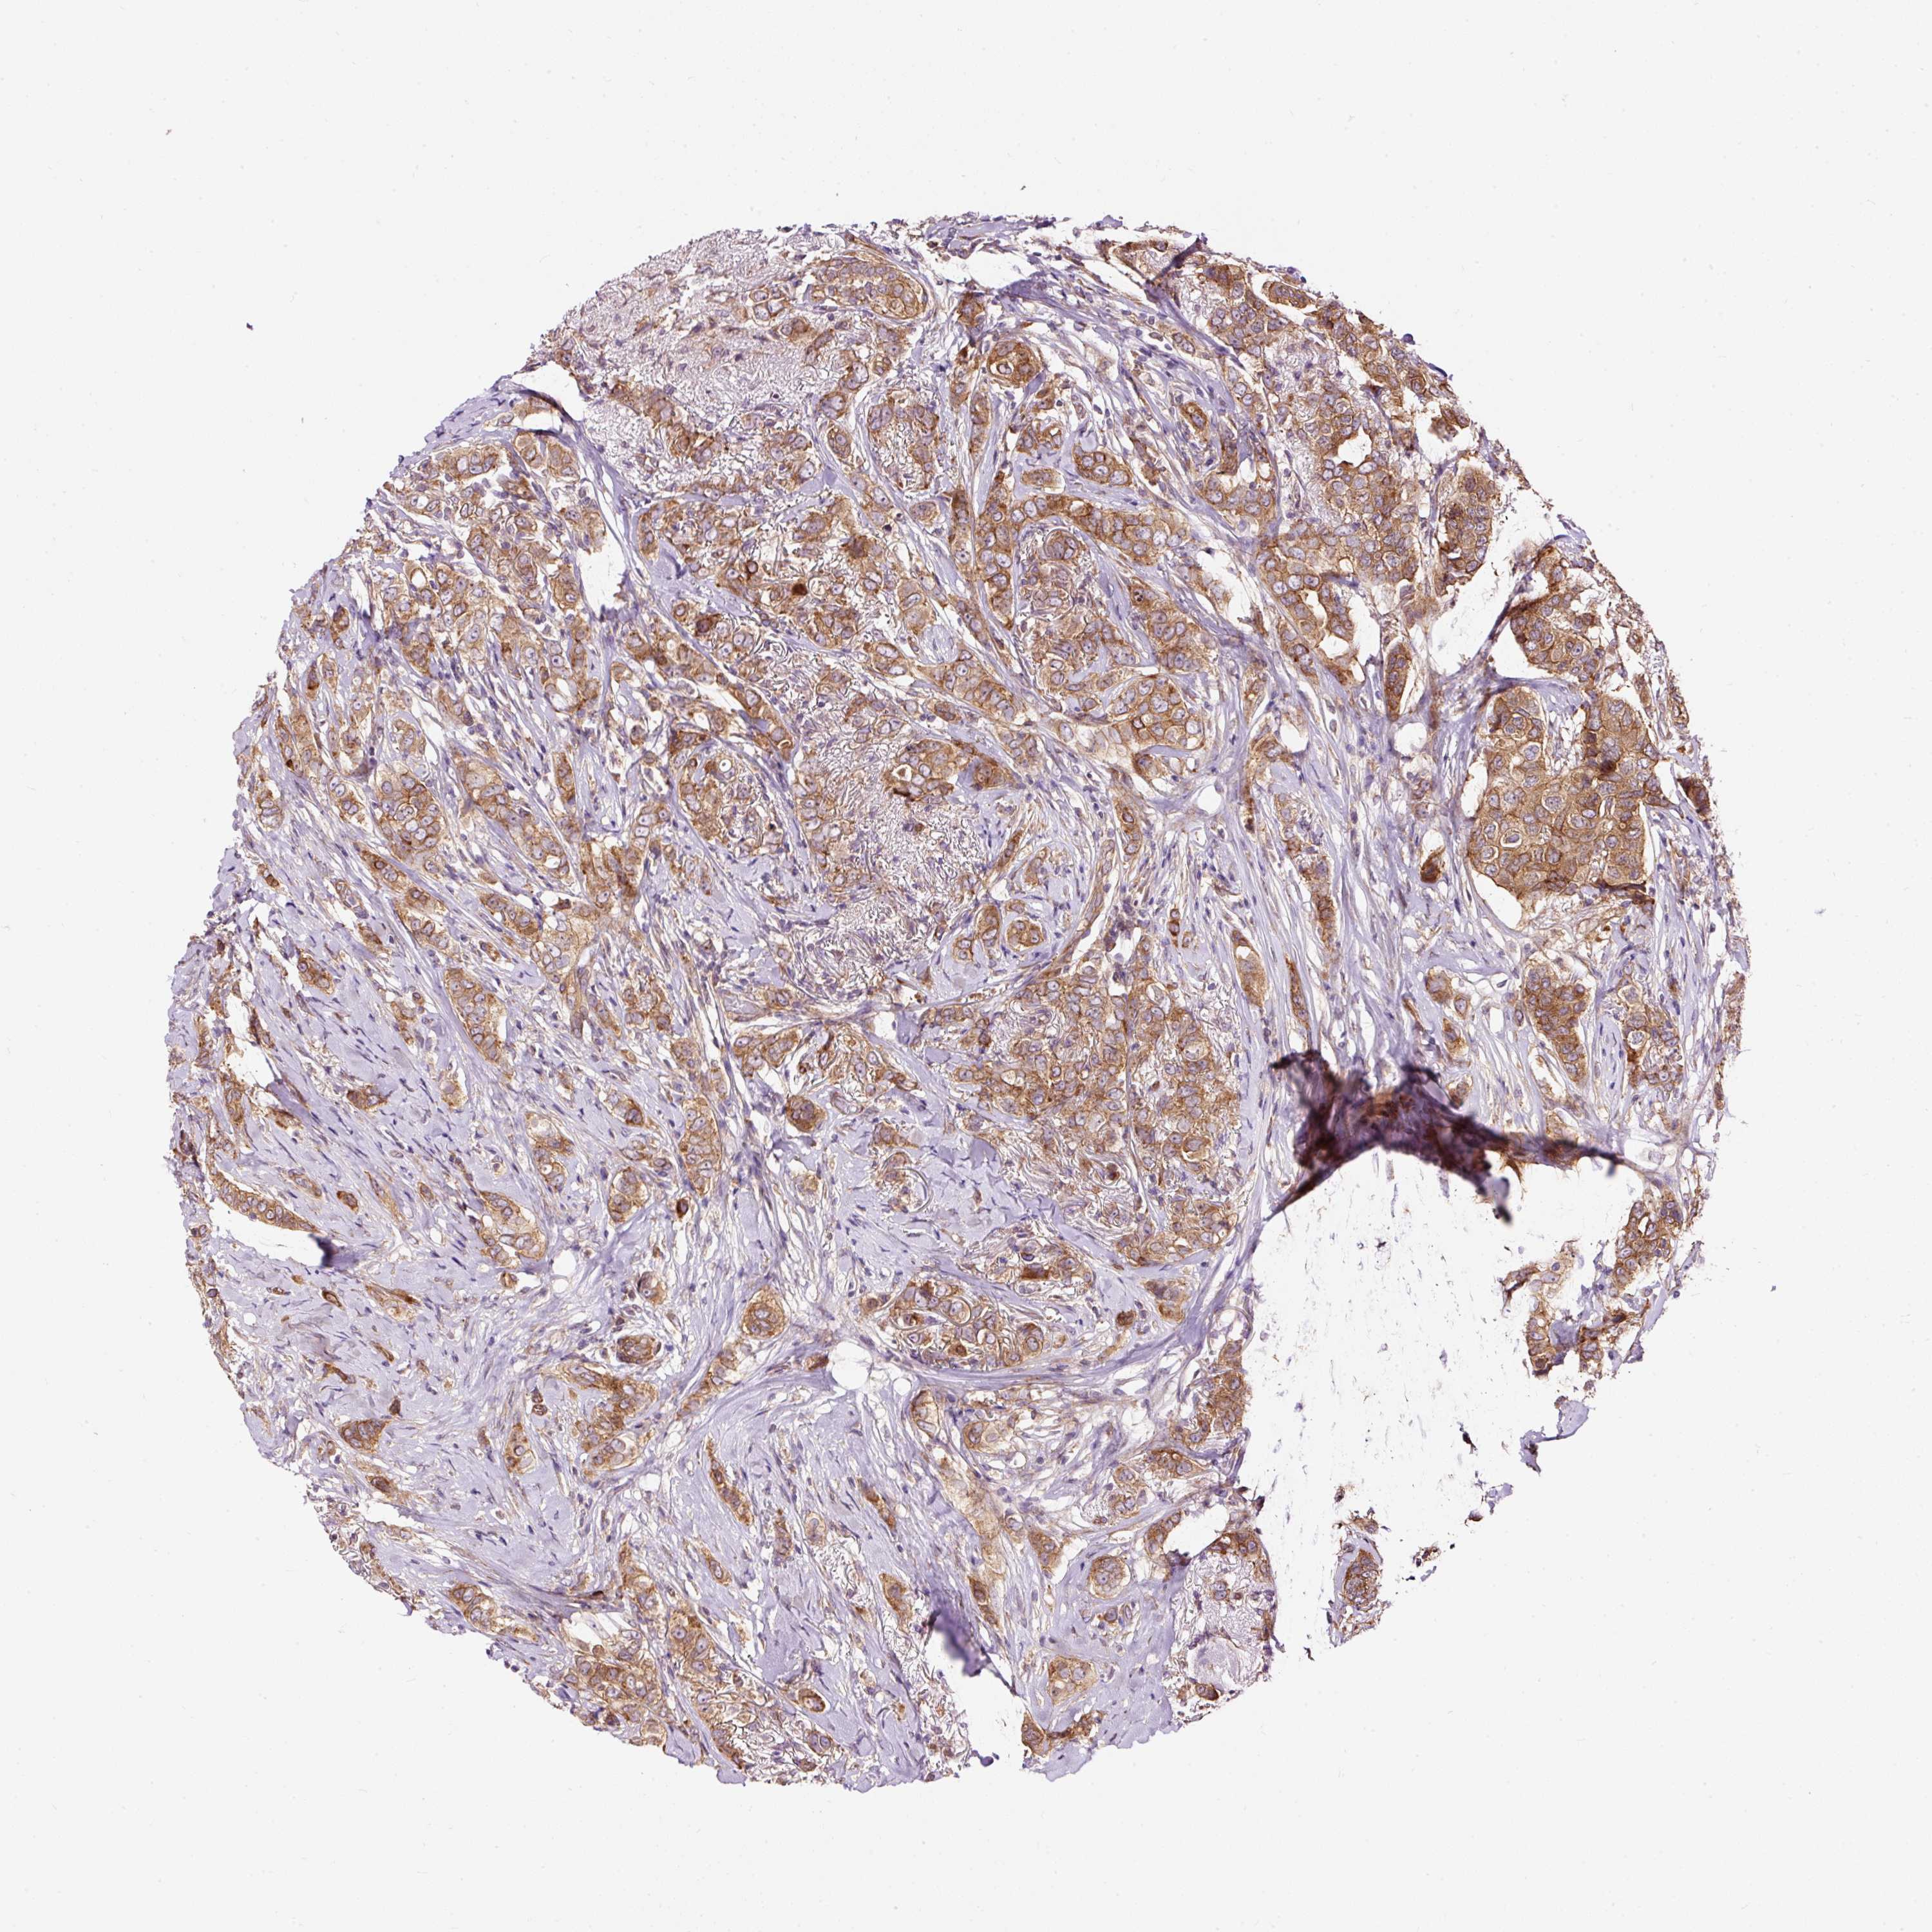

CANCER BREAST CANCER Show tissue menu

BRCA TCGA BRCA VALIDATION PROTEIN EXPRESSION

Breast cancer

Human cancer

Breast invasive carcinoma